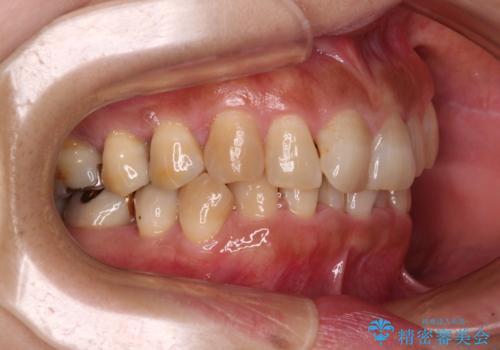

ディープバイトと前歯のデコボコ インビザラインによる矯正治療

- 前歯のディープバイトと叢生を気にして来院された患者様です。

目立ちにくい装置を希望されていたため、ワイヤー装置とインビザラインを提案したところ、インビザラインを希望されました。

下顎大臼歯が手前に倒れていたため、起き上がらせることで咬み合わせ高さを挙上し、ディープバイトと叢生を改善することとしました。